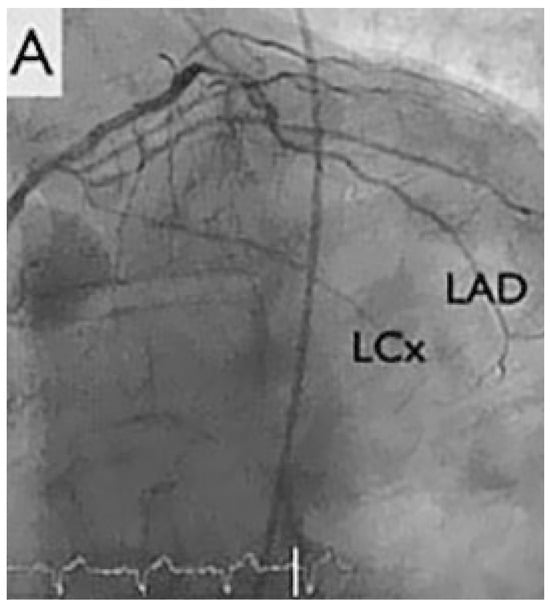

A 67-year-old diabetic patient with three-vessel coronary artery disease (Figure 1) and prior coronary artery bypass graft surgery (left internal mammary artery to left anterior descending artery, vein to marginal branch, vein to right coronary artery) suffered from refractory angina. Coronary angiography demonstrated good results after surgical revascularisation, but also a diffuse infiltration of the left coronary tree. Left ventricular systolic function was normal. The patient presented refractory angina despite optimal antianginal therapy comprising beta-blockers, nitrates, ranolazine (Ranexa®) and molsidomine (Corvaton®). The patient was severely disabled, being unable to walk 200 metres without nitrates, and waking up every 2 hours because of angina and paroxysmal dyspnoea. The treadmill test showed ischaemia.

Figure 1.

Coronary angiogram. LAD: left anterior descending artery, LCx: left circumflex artery, LIMA: left internal mammary artery, MA: marginal artery, RCA: right coronary artery, ous vein graft; LVS: left ventricular tele-systolic volume; LVD: left ventricular tele-diastolic volume.